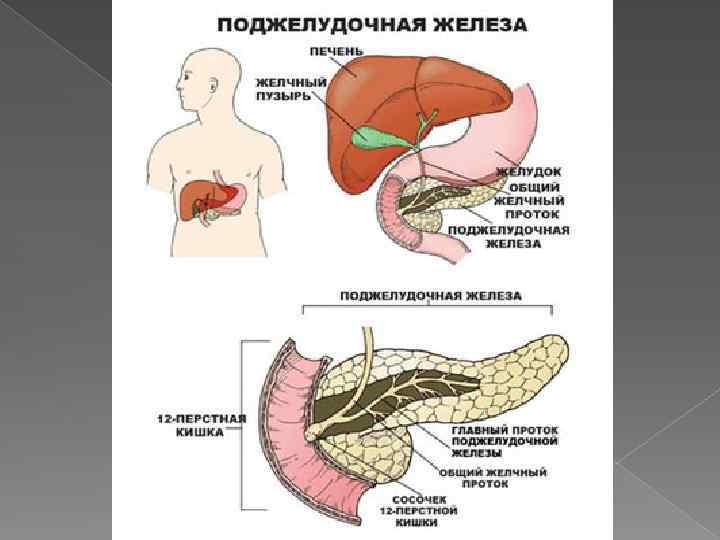

Поджелудочная железа представляет собой большой железистый орган, расположенный позади желудка и сбоку от двенадцатиперстной кишки, причем последняя окутывает ее правую часть подобно подкове.

Поджелудочная железа представляет собой большой железистый орган, расположенный позади желудка и сбоку от двенадцатиперстной кишки, причем последняя окутывает ее правую часть подобно подкове.

Поджелудочная железа находится в забрюшинном пространстве, её головка сращена с двенадцатиперстной кишкой, а хвост находится около селезенки. Длина железы от 14 до 23 см.

Поджелудочная железа находится в забрюшинном пространстве, её головка сращена с двенадцатиперстной кишкой, а хвост находится около селезенки. Длина железы от 14 до 23 см.

Функции: 1. Экзокринная она вырабатывает ферменты, необходимые для переваривания всех без исключения питательных веществ, попавших в кишечник, 2. Эндокринная – выработка инсулина, нехватка которого приводит к сахарному диабету.

Функции: 1. Экзокринная она вырабатывает ферменты, необходимые для переваривания всех без исключения питательных веществ, попавших в кишечник, 2. Эндокринная – выработка инсулина, нехватка которого приводит к сахарному диабету.